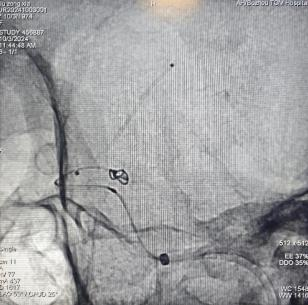

神經(jīng)外科值班醫(yī)生張銀行在詳細(xì)了解患者病情后,決定盡快為患者實(shí)施“腦血管造影術(shù)(DSA)”以確診。DSA結(jié)果清晰顯示:左側(cè)后交通動(dòng)脈瘤,且形狀非常不規(guī)則,大小為4.6mm*2.3mm。

DSA檢查結(jié)果

在與劉女士家屬進(jìn)行了詳細(xì)的病情溝通之后,家屬對(duì)我院表現(xiàn)出了極大的信任,并要求盡快進(jìn)行手術(shù)。經(jīng)過(guò)仔細(xì)且周全的術(shù)前準(zhǔn)備工作后,在麻醉科醫(yī)生王靜和介入導(dǎo)管室周其鈺技師、李景敏護(hù)師的緊密協(xié)作下,腦病中心王磊主任團(tuán)隊(duì)在國(guó)慶假期期間,為劉女士實(shí)施了左側(cè)后交通動(dòng)脈瘤的彈簧圈栓塞術(shù),手術(shù)取得圓滿成功。

術(shù)中填塞動(dòng)脈瘤

動(dòng)脈瘤消失